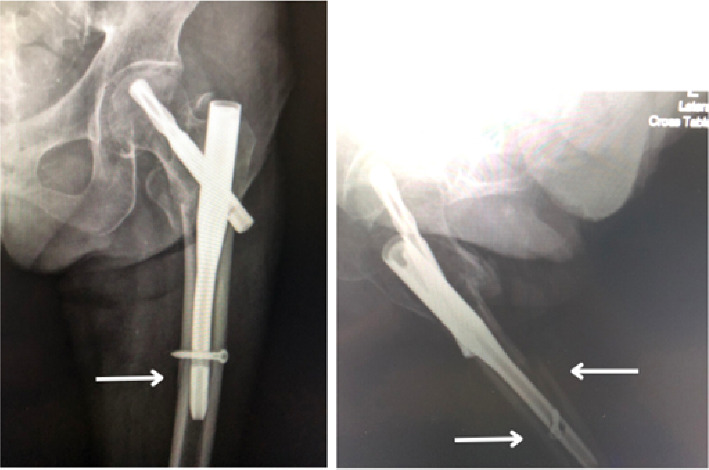

Background: The optimal length of cephalomedullary nails for treating unstable pertrochanteric fractures, particularly in populations with distinct femoral anatomy, remains debated. This study compares the clinical outcomes of using the shortest effective cephalomedullary nails (170 mm) to various short length (200 mm and 240 mm), focusing on Asian patients. Methods: In this randomized controlled trial, 50 patients aged 50 years or older with unstable intertrochanteric fractures (AO types 31A2-3) were randomly assigned to two groups. The shortest-nail group (n = 25) received a 170 mm cephalomedullary nail, while the control group (n = 25) received either a 200 mm or 240 mm nail based on patient height. Primary outcomes were assessed using the Harris Hip Score (HHS) at multiple postsurgery intervals. Secondary outcomes included operative time, hospital stay, hidden blood loss (HBL) (calculated using Sehat's formula), and complication rates. Results: There were no significant differences in HHSs, hospital stay durations, or operative times between the two groups. The median time to fracture union was also comparable between groups (18.1 weeks vs. 18.2 weeks, p=0.9). However, the shortest-nail group showed significantly lower HBL (860.52 mL) compared with the control group (1183.40 mL, p=0.04). Complications included five cases of blade cut-out or refracture, with no significant differences between groups. Conclusion: The shortest effective cephalomedullary nails (170 mm) may offer benefits, particularly in reducing HBL, compared with various short-length nails. However, this advantage may not be solely attributable to nail length, as both groups underwent similar surgical techniques and other factors, such as fracture patterns or patient anatomy, may have influenced the outcomes. While short nails are effective for treating unstable pertrochanteric fractures, larger studies with longer follow-up periods are necessary to validate these findings and assess the long-term safety and efficacy of short nails.